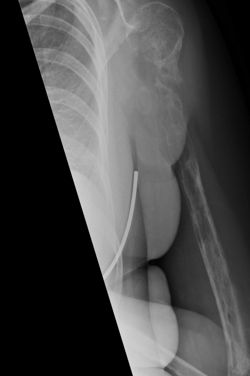

44 yaşlı qadın sol çiynində ağrı ilə klinikaya müraciət edir. Onun çiyin oynağında şişkinlik də var idi. MRT müayinəsi zamanı şiyin sümüyündə patoloji dəyişiklik müşahidə olundu, həkimlər xərçəngdən şübhələnsələr də bu təsdiq olunmur. Sonrakı aylar ərzində sol qolda ağrılar daha da artmağa başlayır, həkimlər isə diaqnoz tapa bilmirlər.

Növbəti MRT çəkimi həkimləri şoka salır: qadının çiyin sümüyü faktiki olaraq əriyib, proses dirsək sümüyünə də keçib. Sümük toxuması əvəzinə dayaq rolunu anomal dərəcədə böyümüş qan damarları əvəz edib. Bundan sonra mütəxəsislər qrup yaradaraq, ümumi razılığa əsasən " Qorem-Staut” sindromu diaqnozunu qoydular. Bu dünyada nadir rast gəlinən patologiyadır. Tibbi ədəbiyyatda bu günə kimi cəmi 64 belə fakt qeydə alınıb. Xəstəliyin səbəbi məlum deyil, həmçinin effektiv müalicəsi də yoxdur.